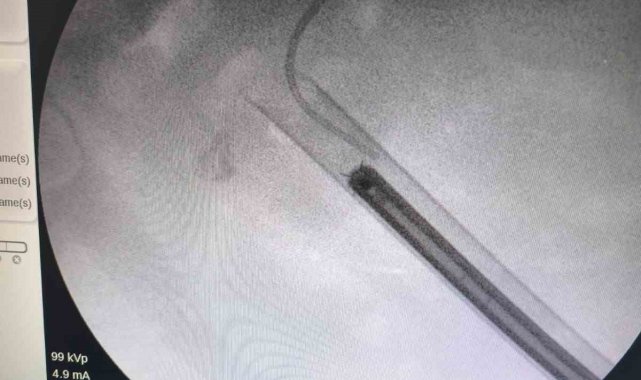

Siirt'te 34 yaşındaki Fatih Aslan, ateş, üşüme ve idrar yaparken yanma şikayetleriyle hastaneye başvurdu. Yapılan muayene ve testlerin ardından piyelonefrit (böbrek iltihabı) tanısı konuldu ve enfeksiyon tedavisi tamamlandı. Üroloji uzmanı doktor Miraç Ataman, gerçekleştirilen operasyon, hem tıbbi açıdan hem de toplumsal sağlık açısından önemli bir başarı olduğunu söyledi. Ataman, "34 yaşındaki erkek hastamız, ateş, üşüme ve idrar yaparken yanma şikayetleri ile acil servise başvurdu. Yapılan değerlendirme sonucunda piyelonefrit (böbrek iltihabı) tanısı konuldu ve yatış yapılarak enfeksiyon tedavisi başarıyla tamamlandı. Tanı sürecinde yapılan Bilgisayarlı Tomografi (BT) görüntülemesinde böbreğin tamamını kaplayan, sert yapıda(950-1450 HU), literatürde staghorn olarak adlandırılan ve halk arasında ' geyik boynuzu taşı ' diye bilinen büyük taş saptandı. Staghorn taşlar böbreğin tüm boşluklarını doldurup, tekrarlayan enfeksiyonlara ve uzun vadede böbrek fonksiyon kaybına yol açabildiğinden tedavisi hayati önem taşımaktadır. Biz de bu vakamızda, Perkütan Nefrolitotomi (PCNL) yöntemiyle böbreğe küçük bir cilt kesisi üzerinden girerek endoskopik cihazlarla taşları parçalayıp çıkardık. PCNL, özellikle çapı 2 cm'den büyük ve kompleks taşlarda altın standart kabul edilmektedir. Normalde staghorn taşların temizlenmesi uzun süren ve çoğu zaman birden fazla seans gerektiren zorlu bir süreçtir. Modern altyapısı sayesinde, ciltten tek giriş yolu açılarak yaklaşık 1,5 saatlik bir seansta böbreğin tüm taş yükü başarıyla temizlendi" dedi.